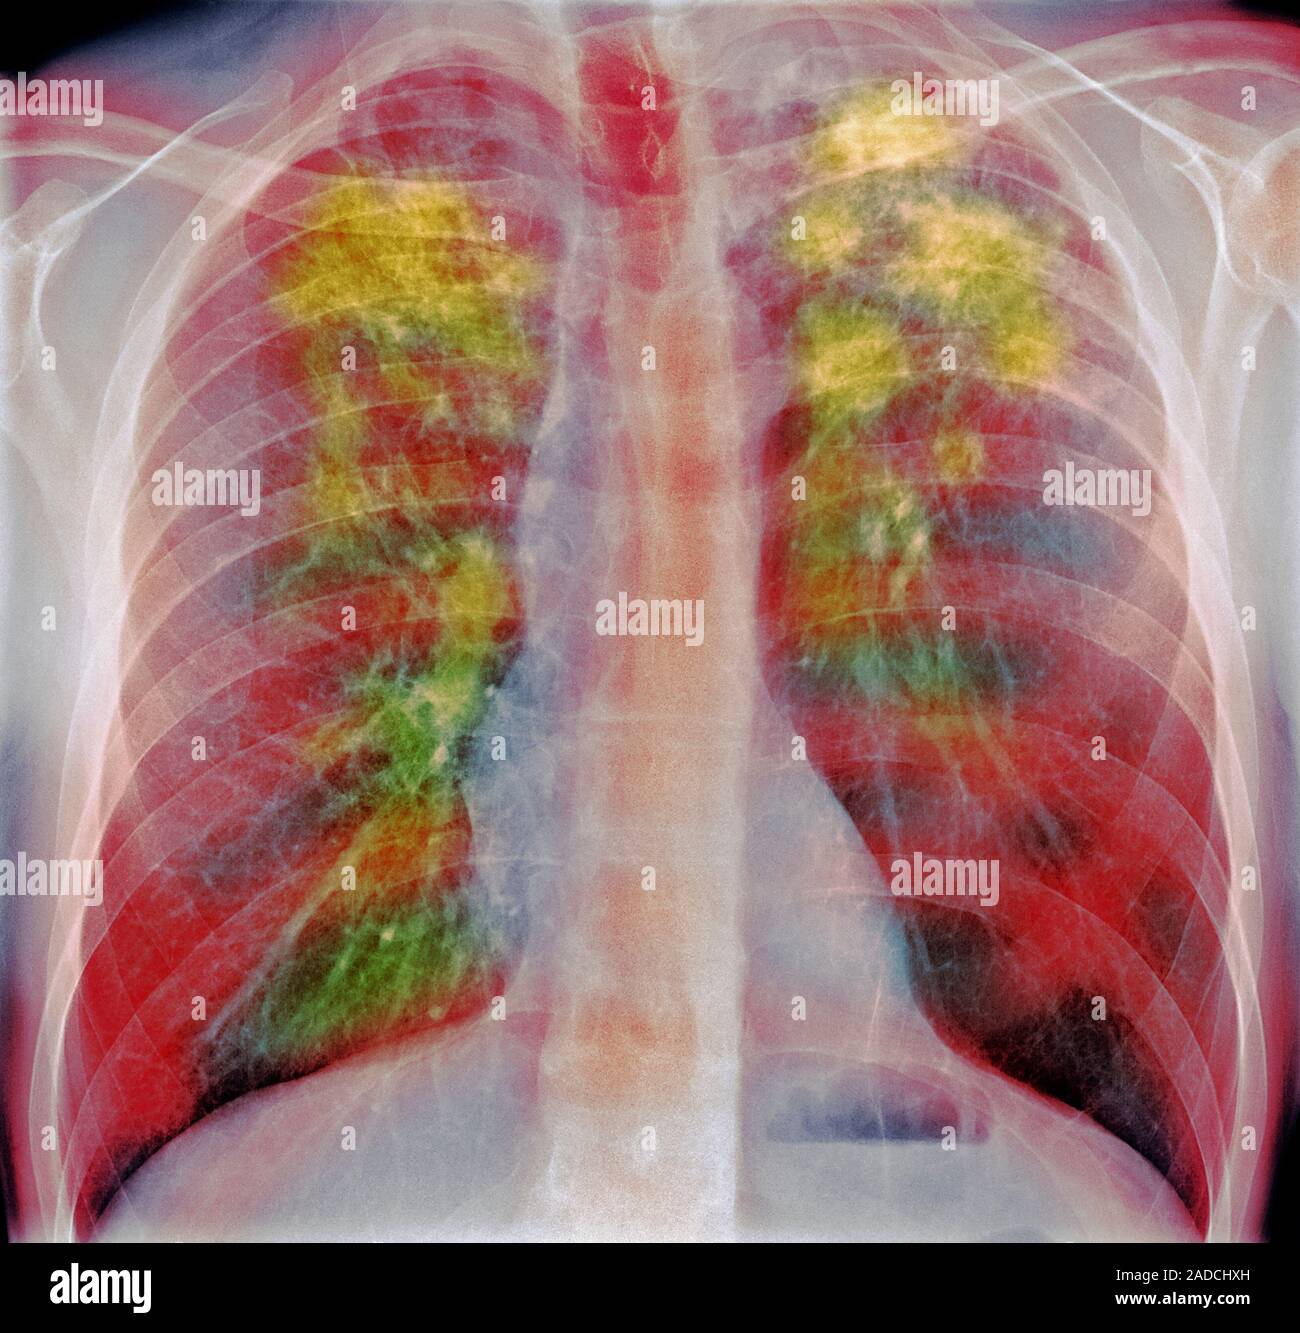

From www.alamy.com

Sarcoidosis. Frontal coloured chest Xray of the lungs of a 52yearold What Does Patch On Lung Mean Because they rarely have symptoms, they are. If your doctor discovers a spot on your lung during an imaging study, you may worry about what it means for your health. These spots are called pulmonary nodules. A spot on the lungs usually refers to a pulmonary nodule. A lung nodule is a small growth in the lung that can show. What Does Patch On Lung Mean.

Sarcoidosis. Frontal coloured chest Xray of the lungs of a 52yearold What Does Patch On Lung Mean A spot on the lungs usually refers to a pulmonary nodule. A lung nodule is a small growth in the lung that can show up on a ct scan. Because they rarely have symptoms, they are. You may have one nodule on the lung or several nodules. These spots are called pulmonary nodules. A lung (pulmonary) nodule is an abnormal. What Does Patch On Lung Mean.